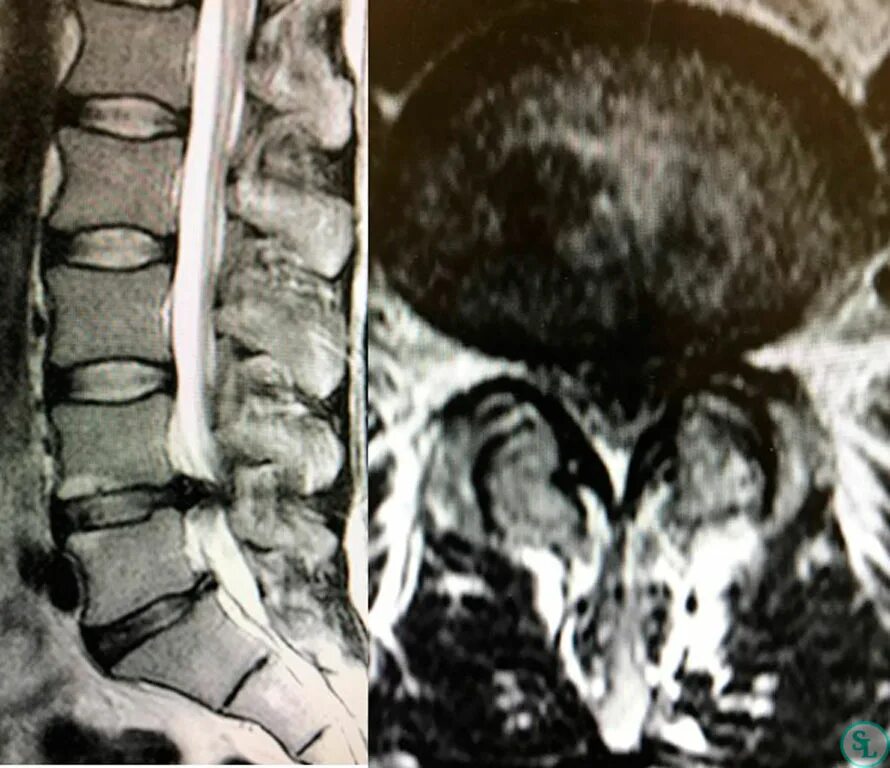

Экструзия дисков позвоночника поясничного l5 s1